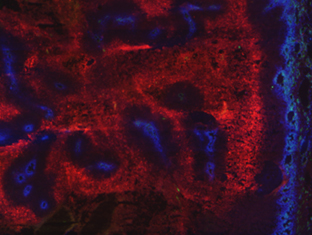

New technology uncovers complexities of colitis-associated colorectal cancer

Digital spatial profiling (DSP) tissue analysis is shedding new light on the molecular changes in colitis-associated colorectal cancer and signalling early biomarkers to identify t